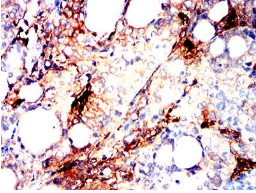

IHC    1/200 - 1/1000